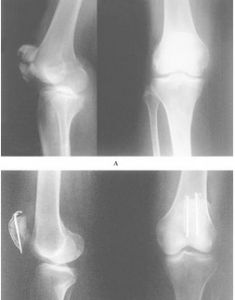

影像學表現:髕骨內可見橫斷或星形的X線透亮的骨折線,由於股四頭肌腱和髕腱的牽扯,骨折塊分離多較明顯,骨折上段向上移位,而下段無移位。如股四頭肌腱沒有完全斷裂,骨折移位較少見。診斷

髕骨正側位X線可確診。對可疑髕骨縱行或邊緣骨折,須拍軸位片證實。併發症

髕骨骨折的治療應最大限度地恢復關節面的平滑,給予較牢固內固定,早期活動膝關節,防止創傷性關節炎的發生。1.非手術治療

髕骨骨折超過2~3毫米移位,關節面不平整超過2毫米,合併伸肌支持帶撕裂骨折,最好採用手術治療。